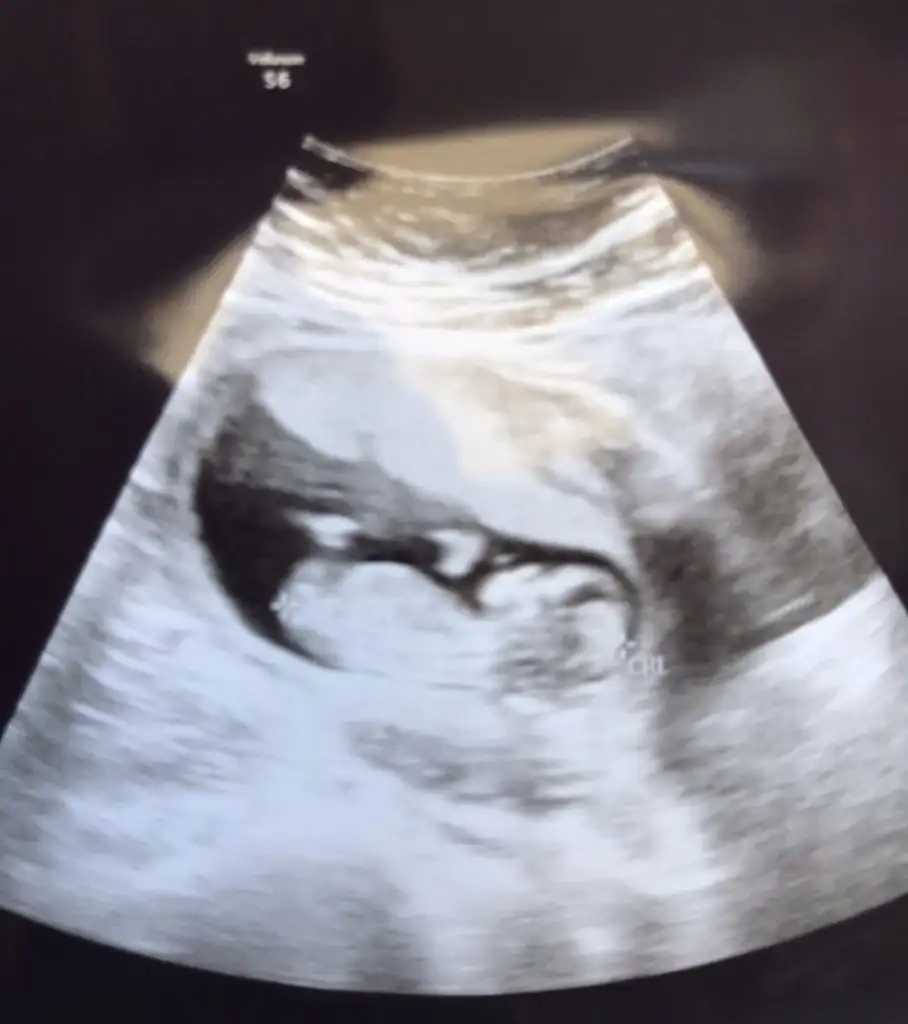

Kaç haftalık erkek dedi dr ben hala kız diyorum dünde baktım bu USG kız gibi nubuMerhaba, buna da bakabilir misiniz?

Kaç haftalık erkek dedi dr ben hala kız diyorum dünde baktım bu USG kız gibi nubu

Şimdi 12+6ydı son gittiğimde. Erkek dedi, güncel resim budur. Benim ilk olduğu için çok farketmiyor aslında sırf merak :))Kaç haftalık erkek dedi dr ben hala kız diyorum dünde baktım bu USG kız gibi nubusağlıkla gelsin minnos

Aaa evet burda kabarık birazda çokta net değil sağlıkla gelsin minnosŞimdi 12+6ydı son gittiğimde. Erkek dedi, güncel resim budur. Benim ilk olduğu için çok farketmiyor aslında sırf merak :))